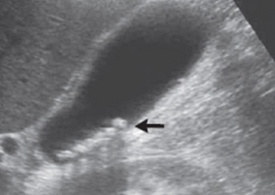

במעבדה אין מאפיינים מיוחדים. האבחנה מתבצעת על-ידי בדיקת אולטרה-סאונד, שהיא בדיקת בחירה לאבחון אבנים בכיס המרה בשל היותה בדיקה בלתי פולשנית בעלת אמינות גבוהה. בבדיקת האולטרה-סאונד יודגמו אבנים בכיס המרה ככתמים בהירים בתוך הכיס, הנעים בשינוי תנוחה. מאחוריהם ניתן לראות את הצל האקוסטי (Acoustic shadow) (תצלום 19.8). שני ממצאים אלה הם הסימנים המובהקים לאבני מרה. בבדיקה זו אפשר לבדוק את קוטר דרכי המרה החוץ-כבדיות. רק 20% מהאבנים בדרכי המרה מודגמות בשיטה זו. כמו-כן אפשר למדוד את קוטר כיס המרה ואורכו. בדיקות אלה אמינות ב- 94%-90%. לעיתים האבנים אינן נראות בברור ב- US אבל נראות ב- אולטרה-סאונד אנדוסקופי (EUS) או מאובחנות ב- CT (תצלום 20.8).

| תצלום 19.8: אבן בכיס המרה (חץ) עם צל אקוסטי בהמשכה. |